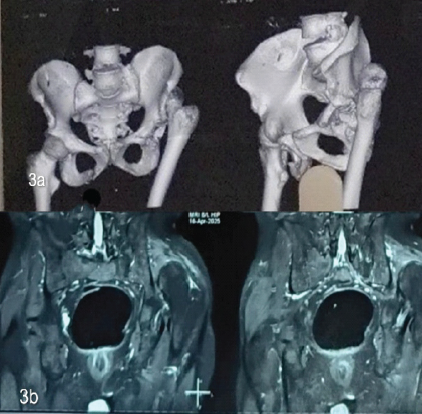

Computed tomography scan and magnetic resonance imaging of the left hip were done to assess the viability of the head. The femoral head was rotated and slightly deformed with complete loss of articular cartilage without any evidence of avascular necrosis of the head of the femur. The posterior wall of the acetabulum appeared fragmented, and the anterior wall was also deformed (Fig. 3).

Figure 3: (a) Computed tomograph Images showing posterior superior dislocation of the left femoral head with the posterior column of left acetabulum appears fragmented; (b) Magnetic resonance imaging images showing complete loss of articular cartilage without any evidence of avascular changes in the femoral head.